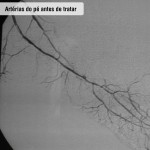

Tratamento endovascular

Pacientes com feridas necessitam de cirurgia na qual é feita punção na virilha, dilatação dos estreitamentos com balão e colocação de stent (molde metálico) para manter a artéria aberta. Com este procedimento, o paciente evita cortes, toma anestesia local e pode voltar para casa no mesmo dia (após seis horas de repouso) ou no dia seguinte. Para evitar novas lesões é imprescindível que a pessoa mude seus hábitos de vida, optando por um estilo mais saudável – inclui-se aí a prática regular de exercícios, a suspensão do fumo e o controle do colesterol e do diabetes.

Doença obstrutiva em diabéticos